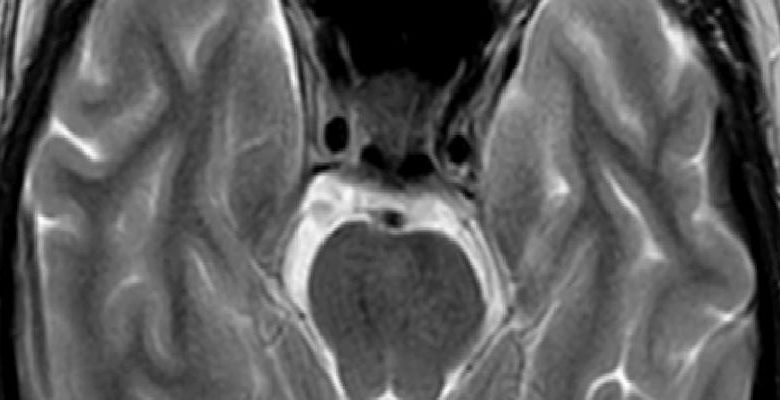

Anlasmali hastanelerde yaptirilan radyolojik görüntüleme testleri: BT; BTA; MRG; MRA; Serebral anjiografi;orbita ve karotis doppler ultrasonografi